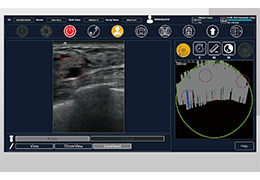

Traditional multi-planar slicing

High-quality and fast 3D reconstruction and 3D rendering

Performs 3D reconstruction and volume rendering.

Multi-planar slicing.

Side-by-side comparative assessment for pre- and post-operative scans.